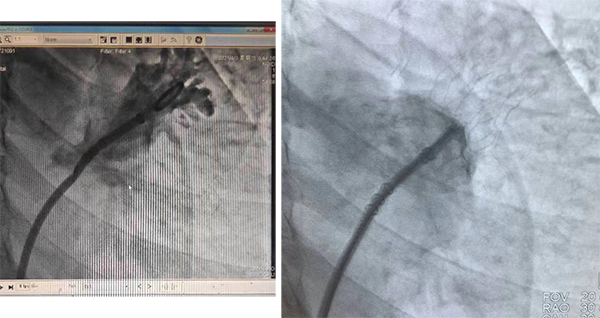

封堵傘術(shù)前、后影像對(duì)比

在介入導(dǎo)管室、麻醉科等多學(xué)科的配合幫助下,王又平主任通過(guò)微創(chuàng)的方法,將傘形MemoLefort封堵器發(fā)放至患者左心耳根部,成功為患者完成經(jīng)導(dǎo)管左心耳封堵術(shù),術(shù)后患者無(wú)不適,復(fù)查超聲左心耳完全封堵,無(wú)分流現(xiàn)象。